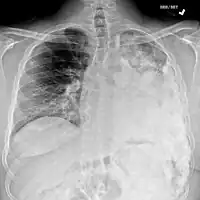

Most times, the early signs of osteosarcoma are caught on X-rays taken during routine dental check-ups. Osteosarcoma frequently develops in the mandible (lower jaw); accordingly, dentists are trained to look for signs that may suggest osteosarcoma. Even though radiographic findings for this cancer vary greatly, one usually sees a symmetrical widening of the periodontal ligament space. If the dentist has reason to suspects osteosarcoma or another underlying disorder, he or she would refer the person to an Oral & Maxillofacial surgeon for biopsy. A biopsy of suspected osteosarcoma outside of the facial region should be performed by a qualified orthopedic oncologist. The American Cancer Society states: "Probably in no other cancer is it as important to perform this procedure properly. An improperly performed biopsy may make it difficult to save the affected limb from amputation." It may also metastasise to the lungs, mainly appearing on the chest X-ray as solitary or multiple round nodules most common at the lower regions.